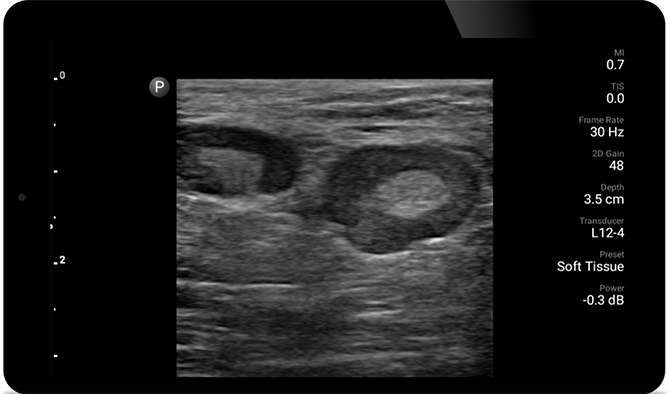

Ultrasound exams can improve your ability to identify and successfully treat skin abscesses.

POC ultrasound for soft tissue